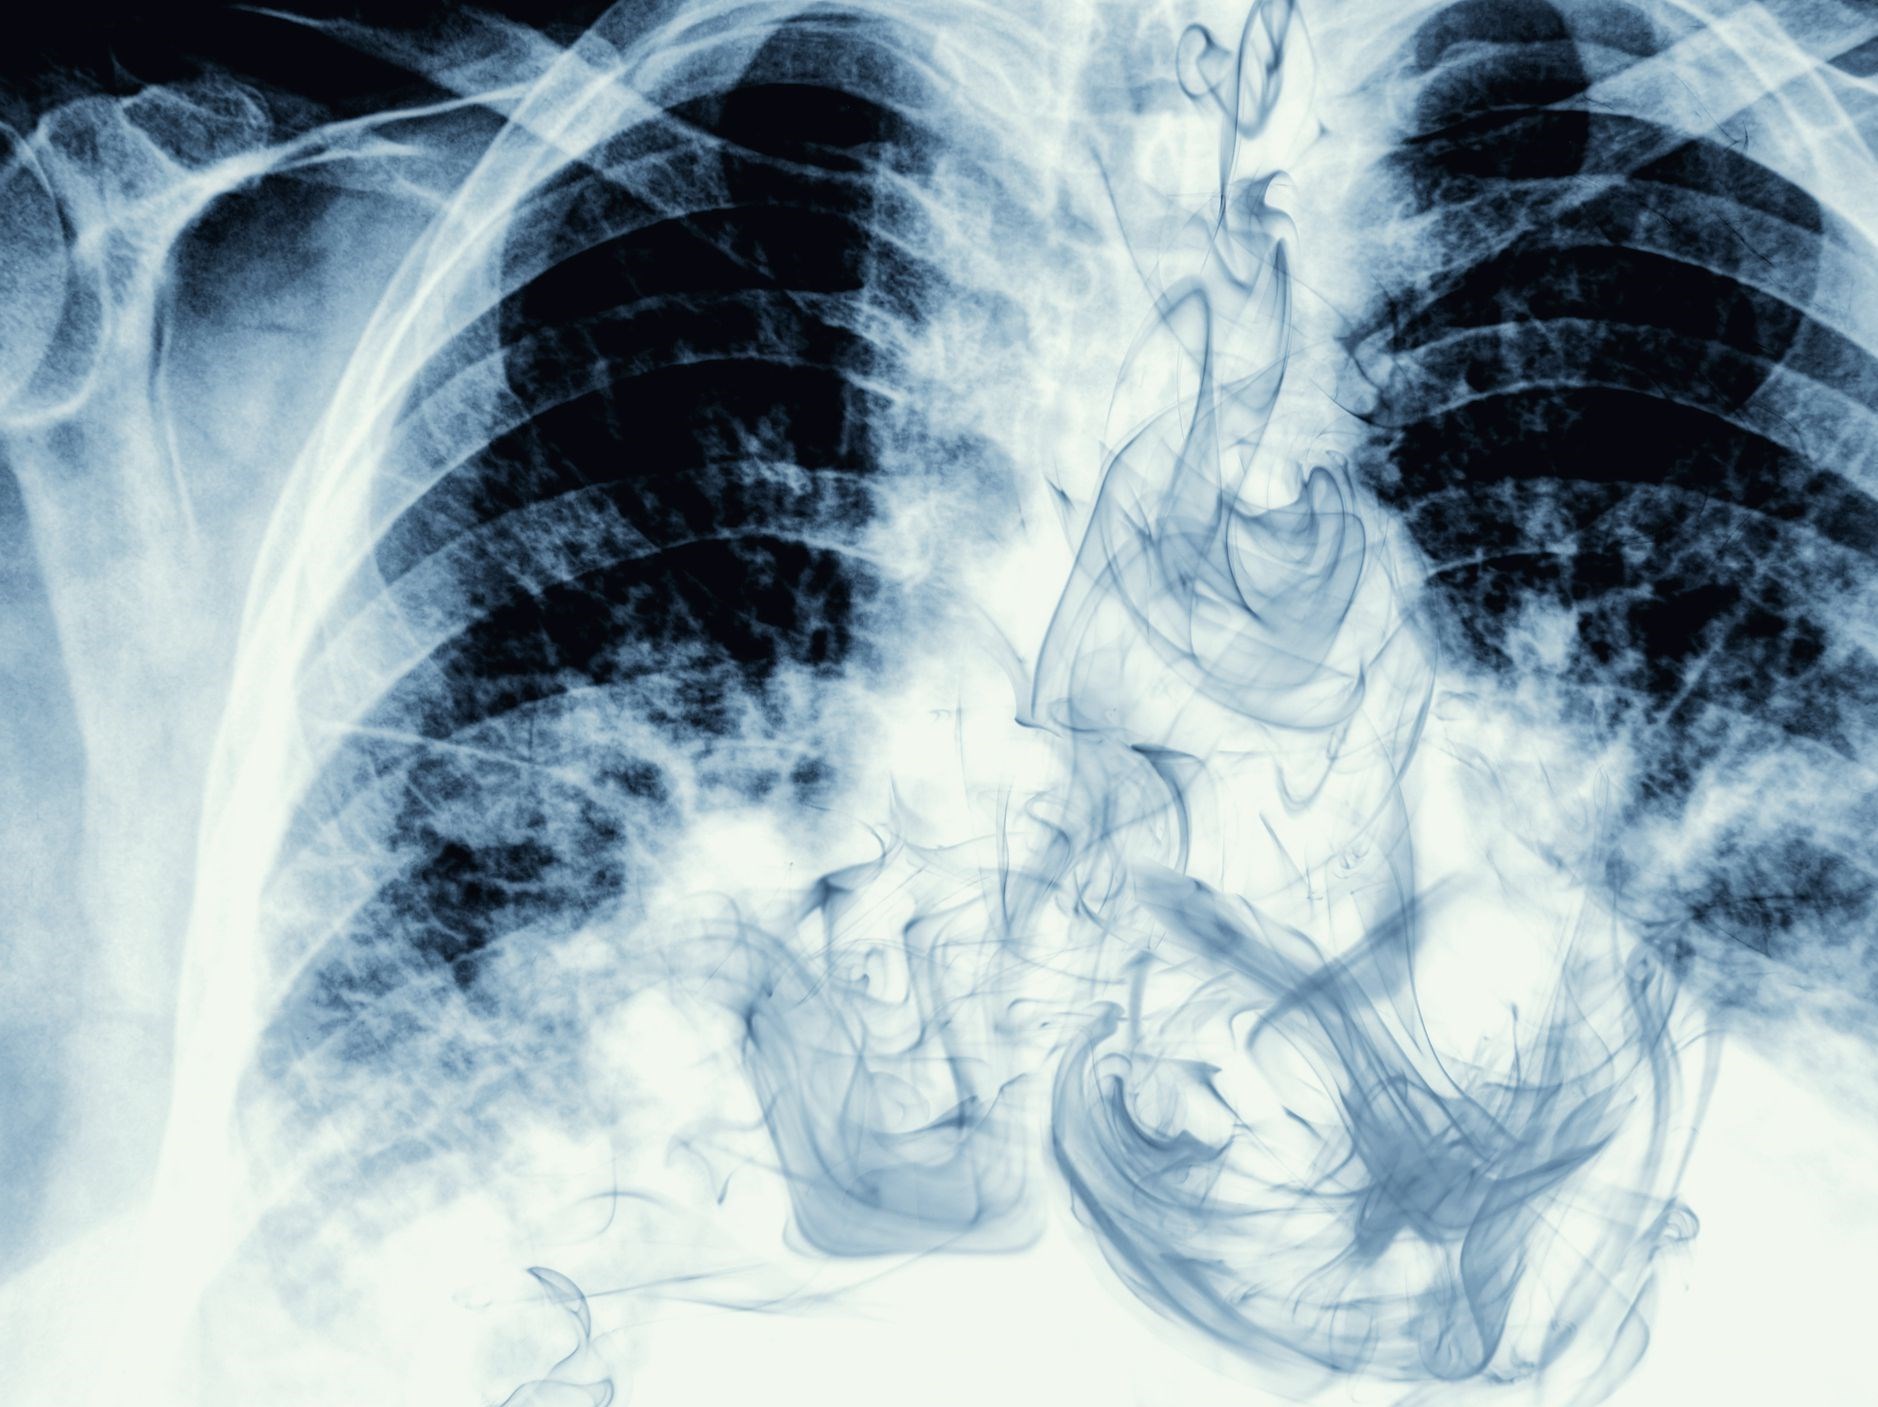

در این باره گزارشی توسط "world bank" منتشر میشود که طبق آن 80 درصد تلفات ناشی از بیماری سرطان ریه مربوط به استعمال دخانیات است و همچنین 25 درصد از قربانیان بیماریهای قلبی را افراد سیگاری تشکیل میدهند.

همچنین طبق گفته محققان افراد سیگاری بیشتر از دیگران مستعد ابتلا به ویروس کرونا بوده و بیشتر قربانی این ویروس میشوند؛ شواهد کشورهای چین و ایتالیا حاکی از آن است که افراد سیگاری در مقایسه با غیرسیگاریها در پیشرفت ویروس کرونا شدت بیشتری دارند؛ همچنین هزینههای مراقبتهای بهداشتی قابل توجهی برای درمان آنها صرف میشود.

طبق گفته سازمان بهداشت جهانی همه اشکال توتون و تنباکو مضر است و هیچ سطح مطمئنی از قرار گرفتن در معرض دخانیات وجود ندارد؛ کشیدن سیگار از رایج ترین شکل مصرف دخانیات در سراسر جهان است که باعث افزایش بیماریهای قلبی و ریوی در بین استعمال کنندگان شده است.